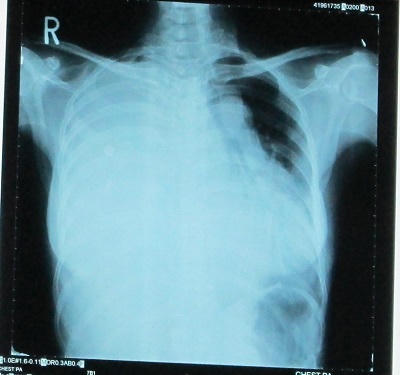

Các bác sĩ khoa Ngoại lồng ngực tại Bệnh viện Chợ Rẫy (TP.Hồ Chí Minh) cho biết, họ vừa cắt bỏ thành công khối u sợi thần kinh nằm cạnh tim bệnh nhân Nguyễn Thị Phượng thành công. Đây được xem là khối u hiếm gặp từ trước đến nay.

Bác sĩ Vũ Hữu Vĩnh, Trưởng khoa cho hay, khối u không những có kích thước lớn (30x70x25cm) mà còn rất cứng do được cấu thành từ những dây thần kinh liên sườn. “Cũng có những trường hợp u lớn nhưng mềm, còn u lớn và cứng rất hiếm gặp. Để cắt bỏ khối u, chúng tôi đã tiến hành phẫu thuật chẻ xương ức và mở ngực phải. Trước đó, chúng tôi đã tách và dịch chuyển các mạch máu ra khỏi vị trí khối u”, bác sĩ Vĩnh nói.

Quá trình lấy khối u ra ngoài gặp nhiều khó khăn do u được nuôi bằng mạch máu chính, dính chặt vào cơ hoành, màng tim và đè bẹp toàn bộ phần phổi bên phải. Bởi vậy, nếu quá trình phẫu thuật không cẩn trọng, rất dễ dẫn đến tình trạng mất máu cấp gây nguy hiểm tính mạng bệnh nhân.